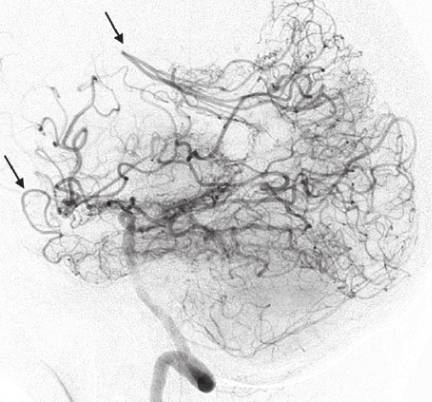

모야모야병이라는 질환의 이름은 정상 혈관이 좁아지면서 부족한 혈류량을 공급하기 위해 생긴 비정상적인 미세혈관이 마치 ‘담배 연기가 모락모락 올라가는 모양’과 비슷하다고 해서 붙은 이름이다. 1969년 일본 스즈키 교수가 ‘모락모락’이라는 뜻의 일본어 ‘모야모야(もやもや)’에서 착안해 이름을 지었다.

모야모야병은 우리나라와 일본에서 상대적으로 자주 발생하고 서양에서는 보기 힘든 질환이다. 또 여성에서 약 1.8배 더 많고, 10세 전후 소아와 40~50대 성인에서 상대적으로 흔하게 발생한다. 소아 모야모야병은 빨리 진행하고, 성인 모야모야병은 다소 천천히 진행하는 양상을 보이는데, 모야모야병의 증상이 갑자기 악화하는 이유는 아직 명확하게 밝혀지지 않은 상태다.